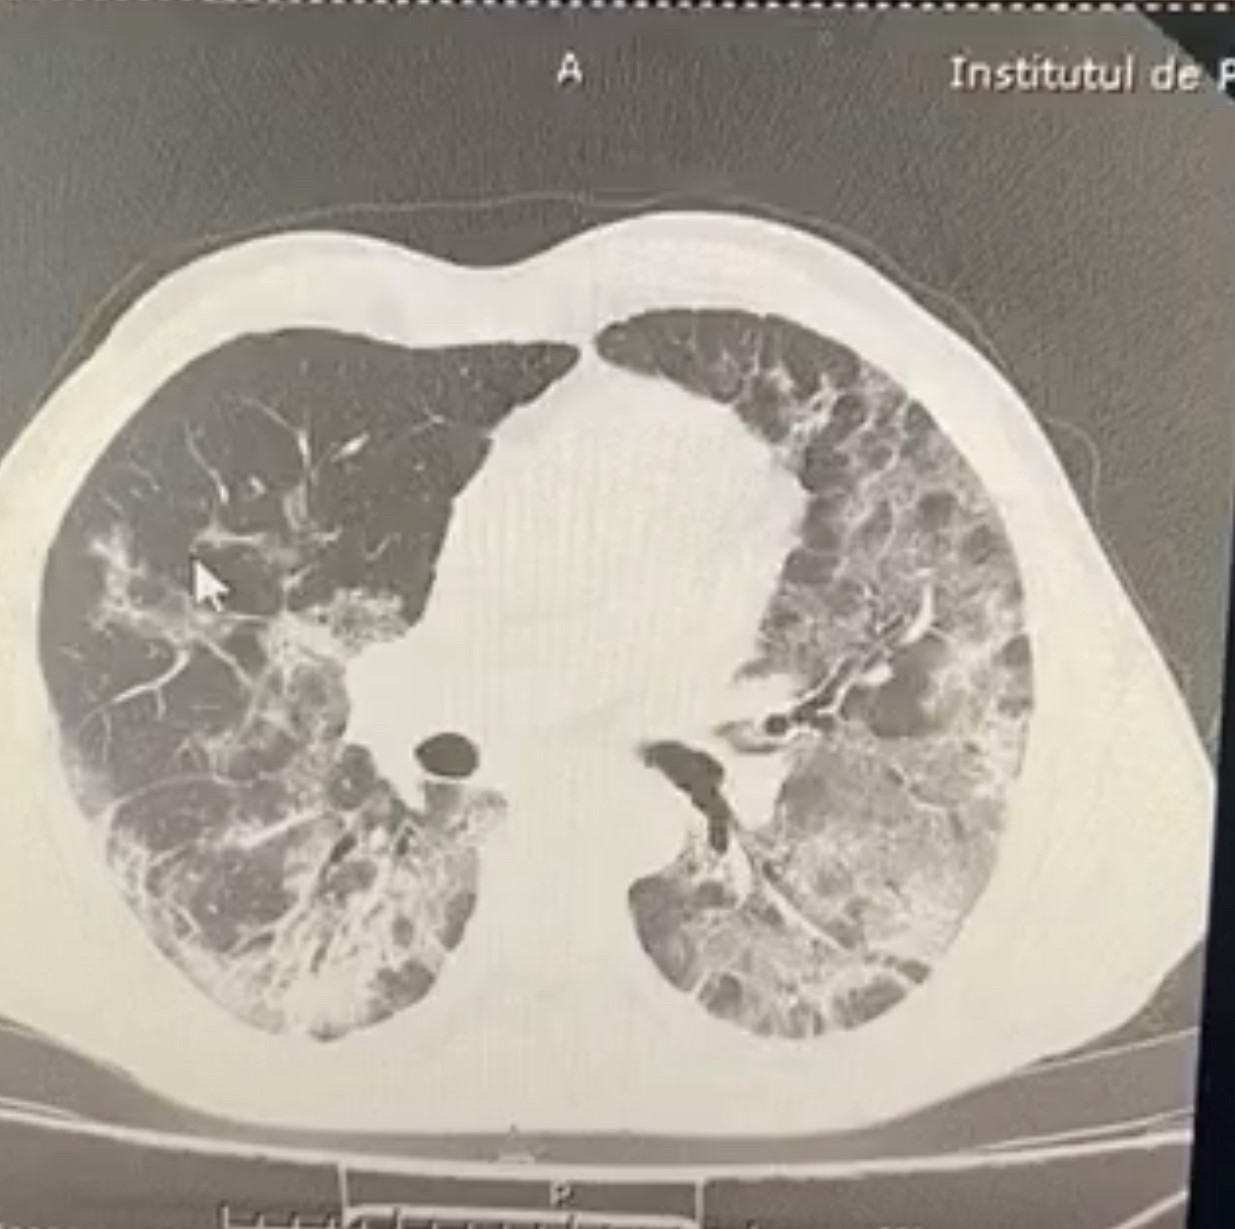

Imagine CT torace la pacient admis în secția de pneumologie, imediat după negativarea infecției SARS-CoV-2. Se observă leziuni cu tendință evolutivă spre fibrozare mai ales la baza dreaptă, cu tendință de retracție și dezvoltare de bronșiectazii.